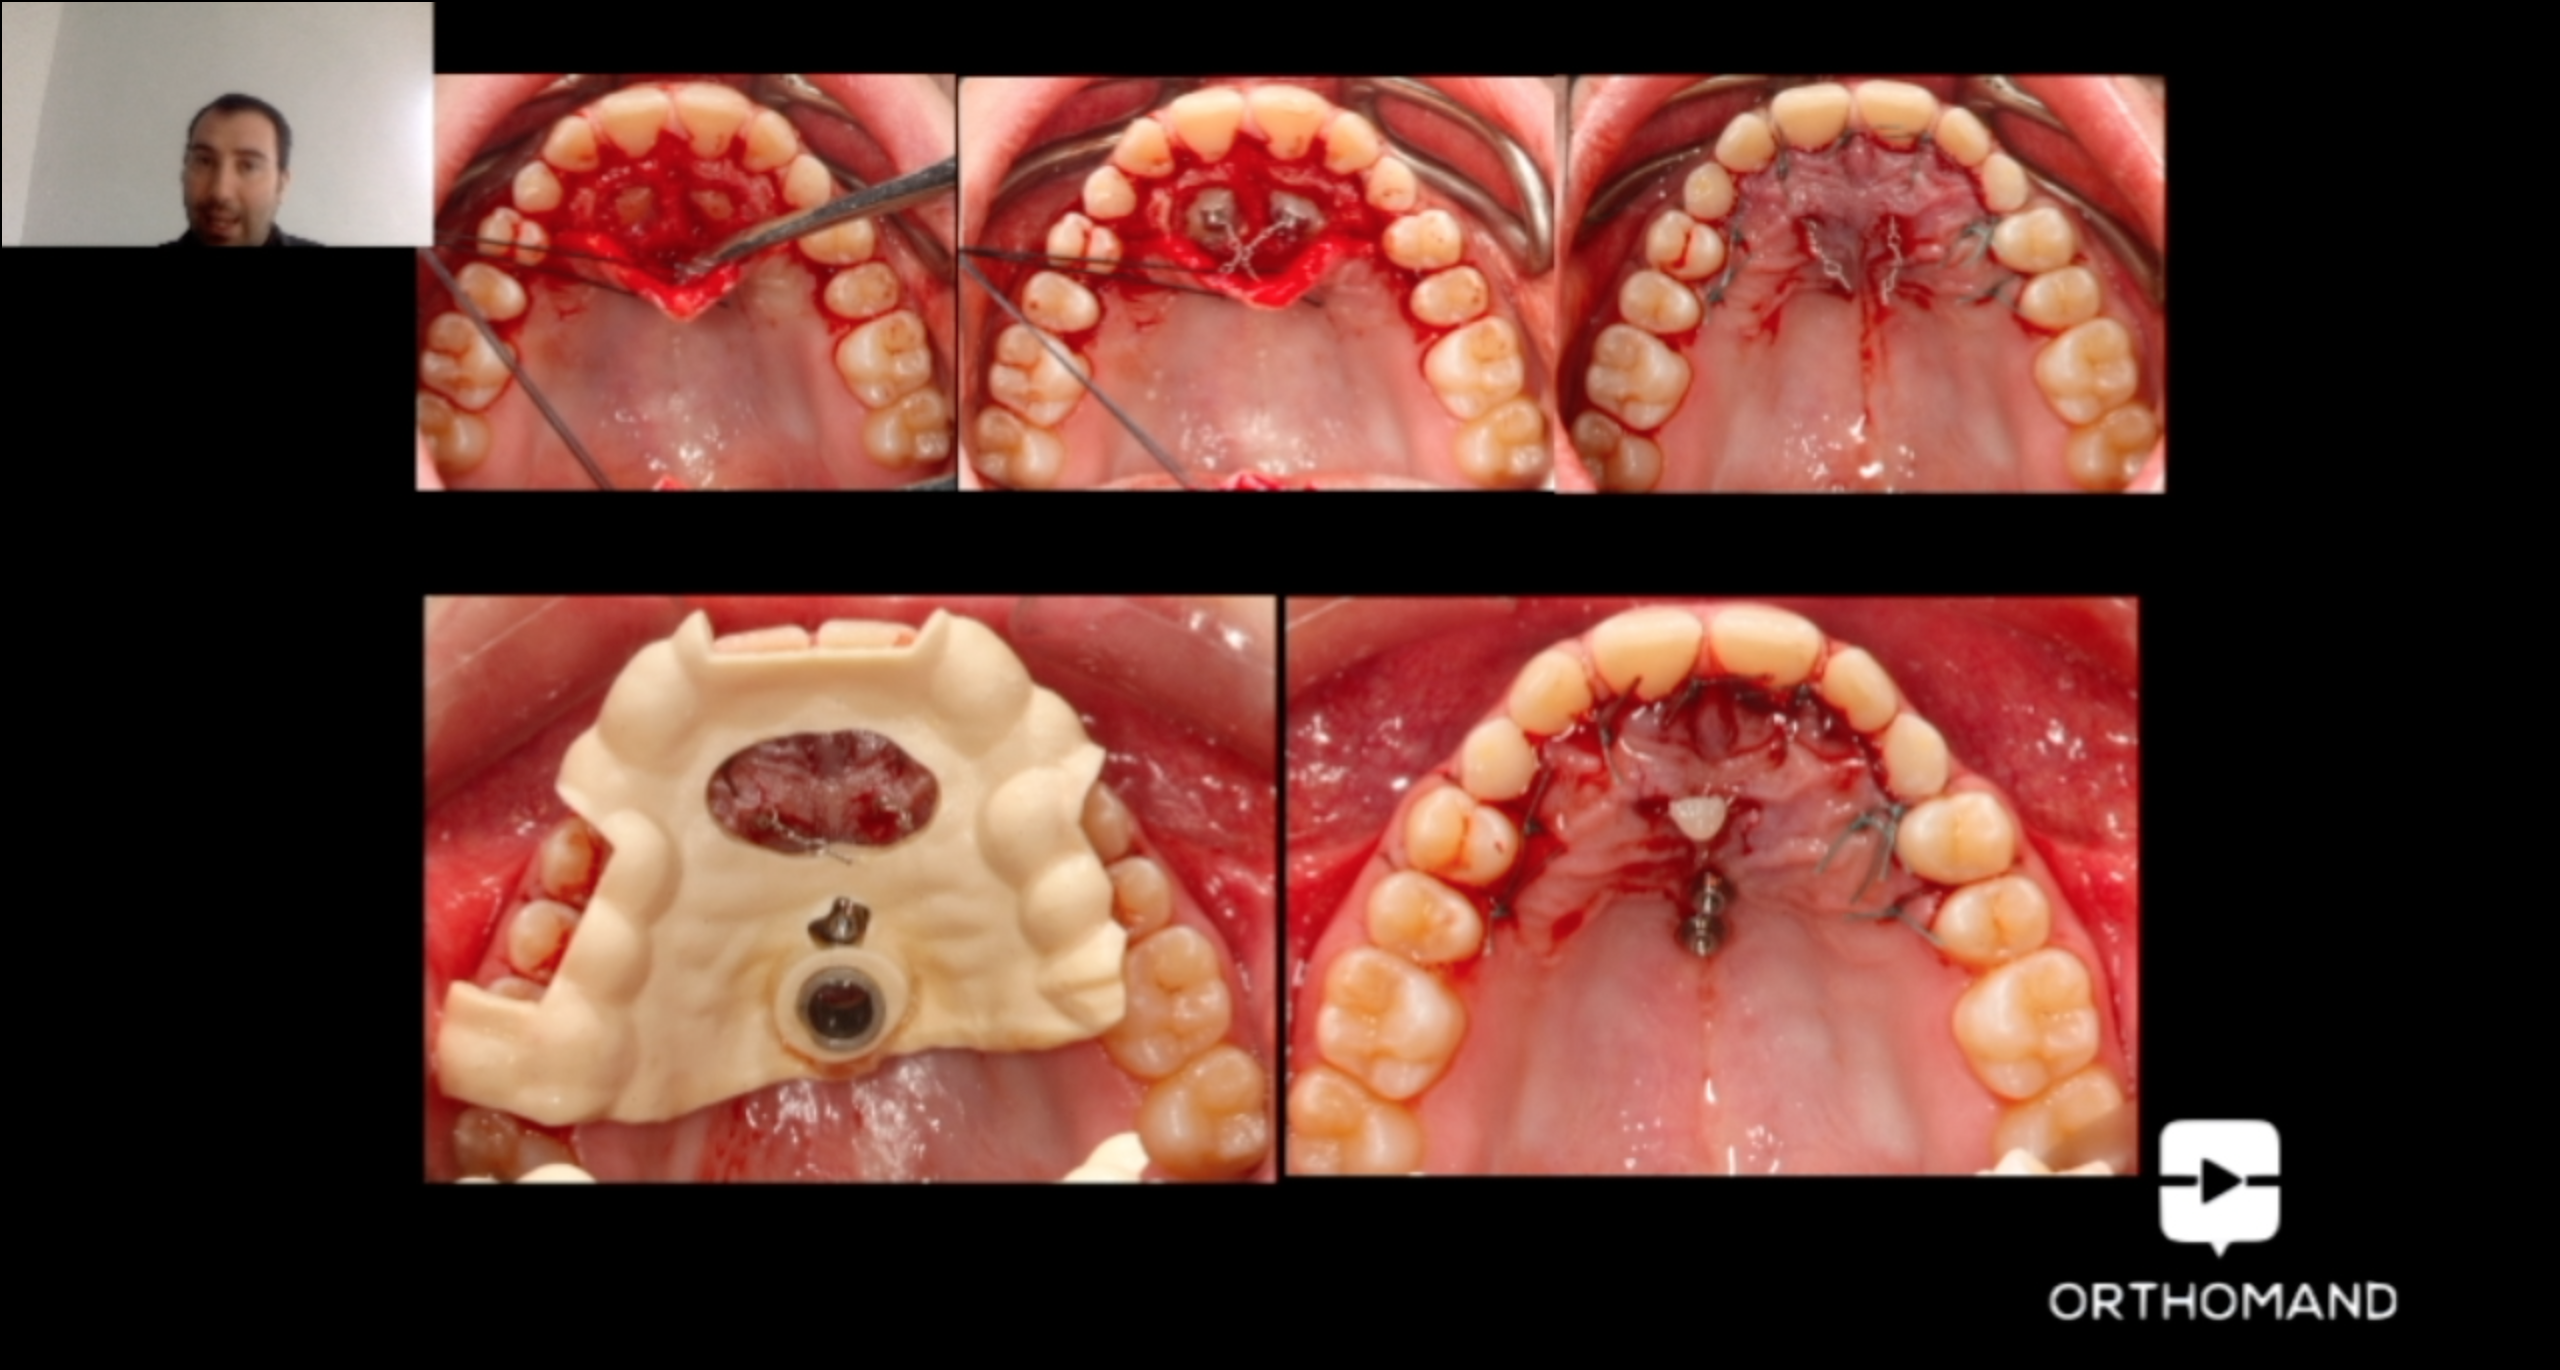

La disinclusione del canino palatale rappresenta una vera sfida per l’ortodontista. Molte tecniche classicamente utilizzate mostrano rischi e limiti di predicibilità clinica. La finalità del corso è esporre un nuovo approccio di trattamento all’inclusione palatale del canino. Attraverso la scelta di ancoraggi scheletrici e di meccaniche segmentate è possibile trattare in maniera predicibile, efficiente ed efficace tale rilevante problematica ortodontica riducendo molti classici effetti avversi, senza alcun impatto estetico e di compliance del paziente. Il workflow digitale fornisce, inoltre, un valore aggiunto in termini di pianificazione dell’ancoraggio scheletrico, di piena individualizzazione del dispositivo ortodontico e di aiuto nella gestione segmentata della tecnica di disinclusione.

- Come disegnare dispositivi digitali customizzati di disinclusione

- Modellare i sezionali di disinclusione e di traslazione vestibolare

Estratti dal corso